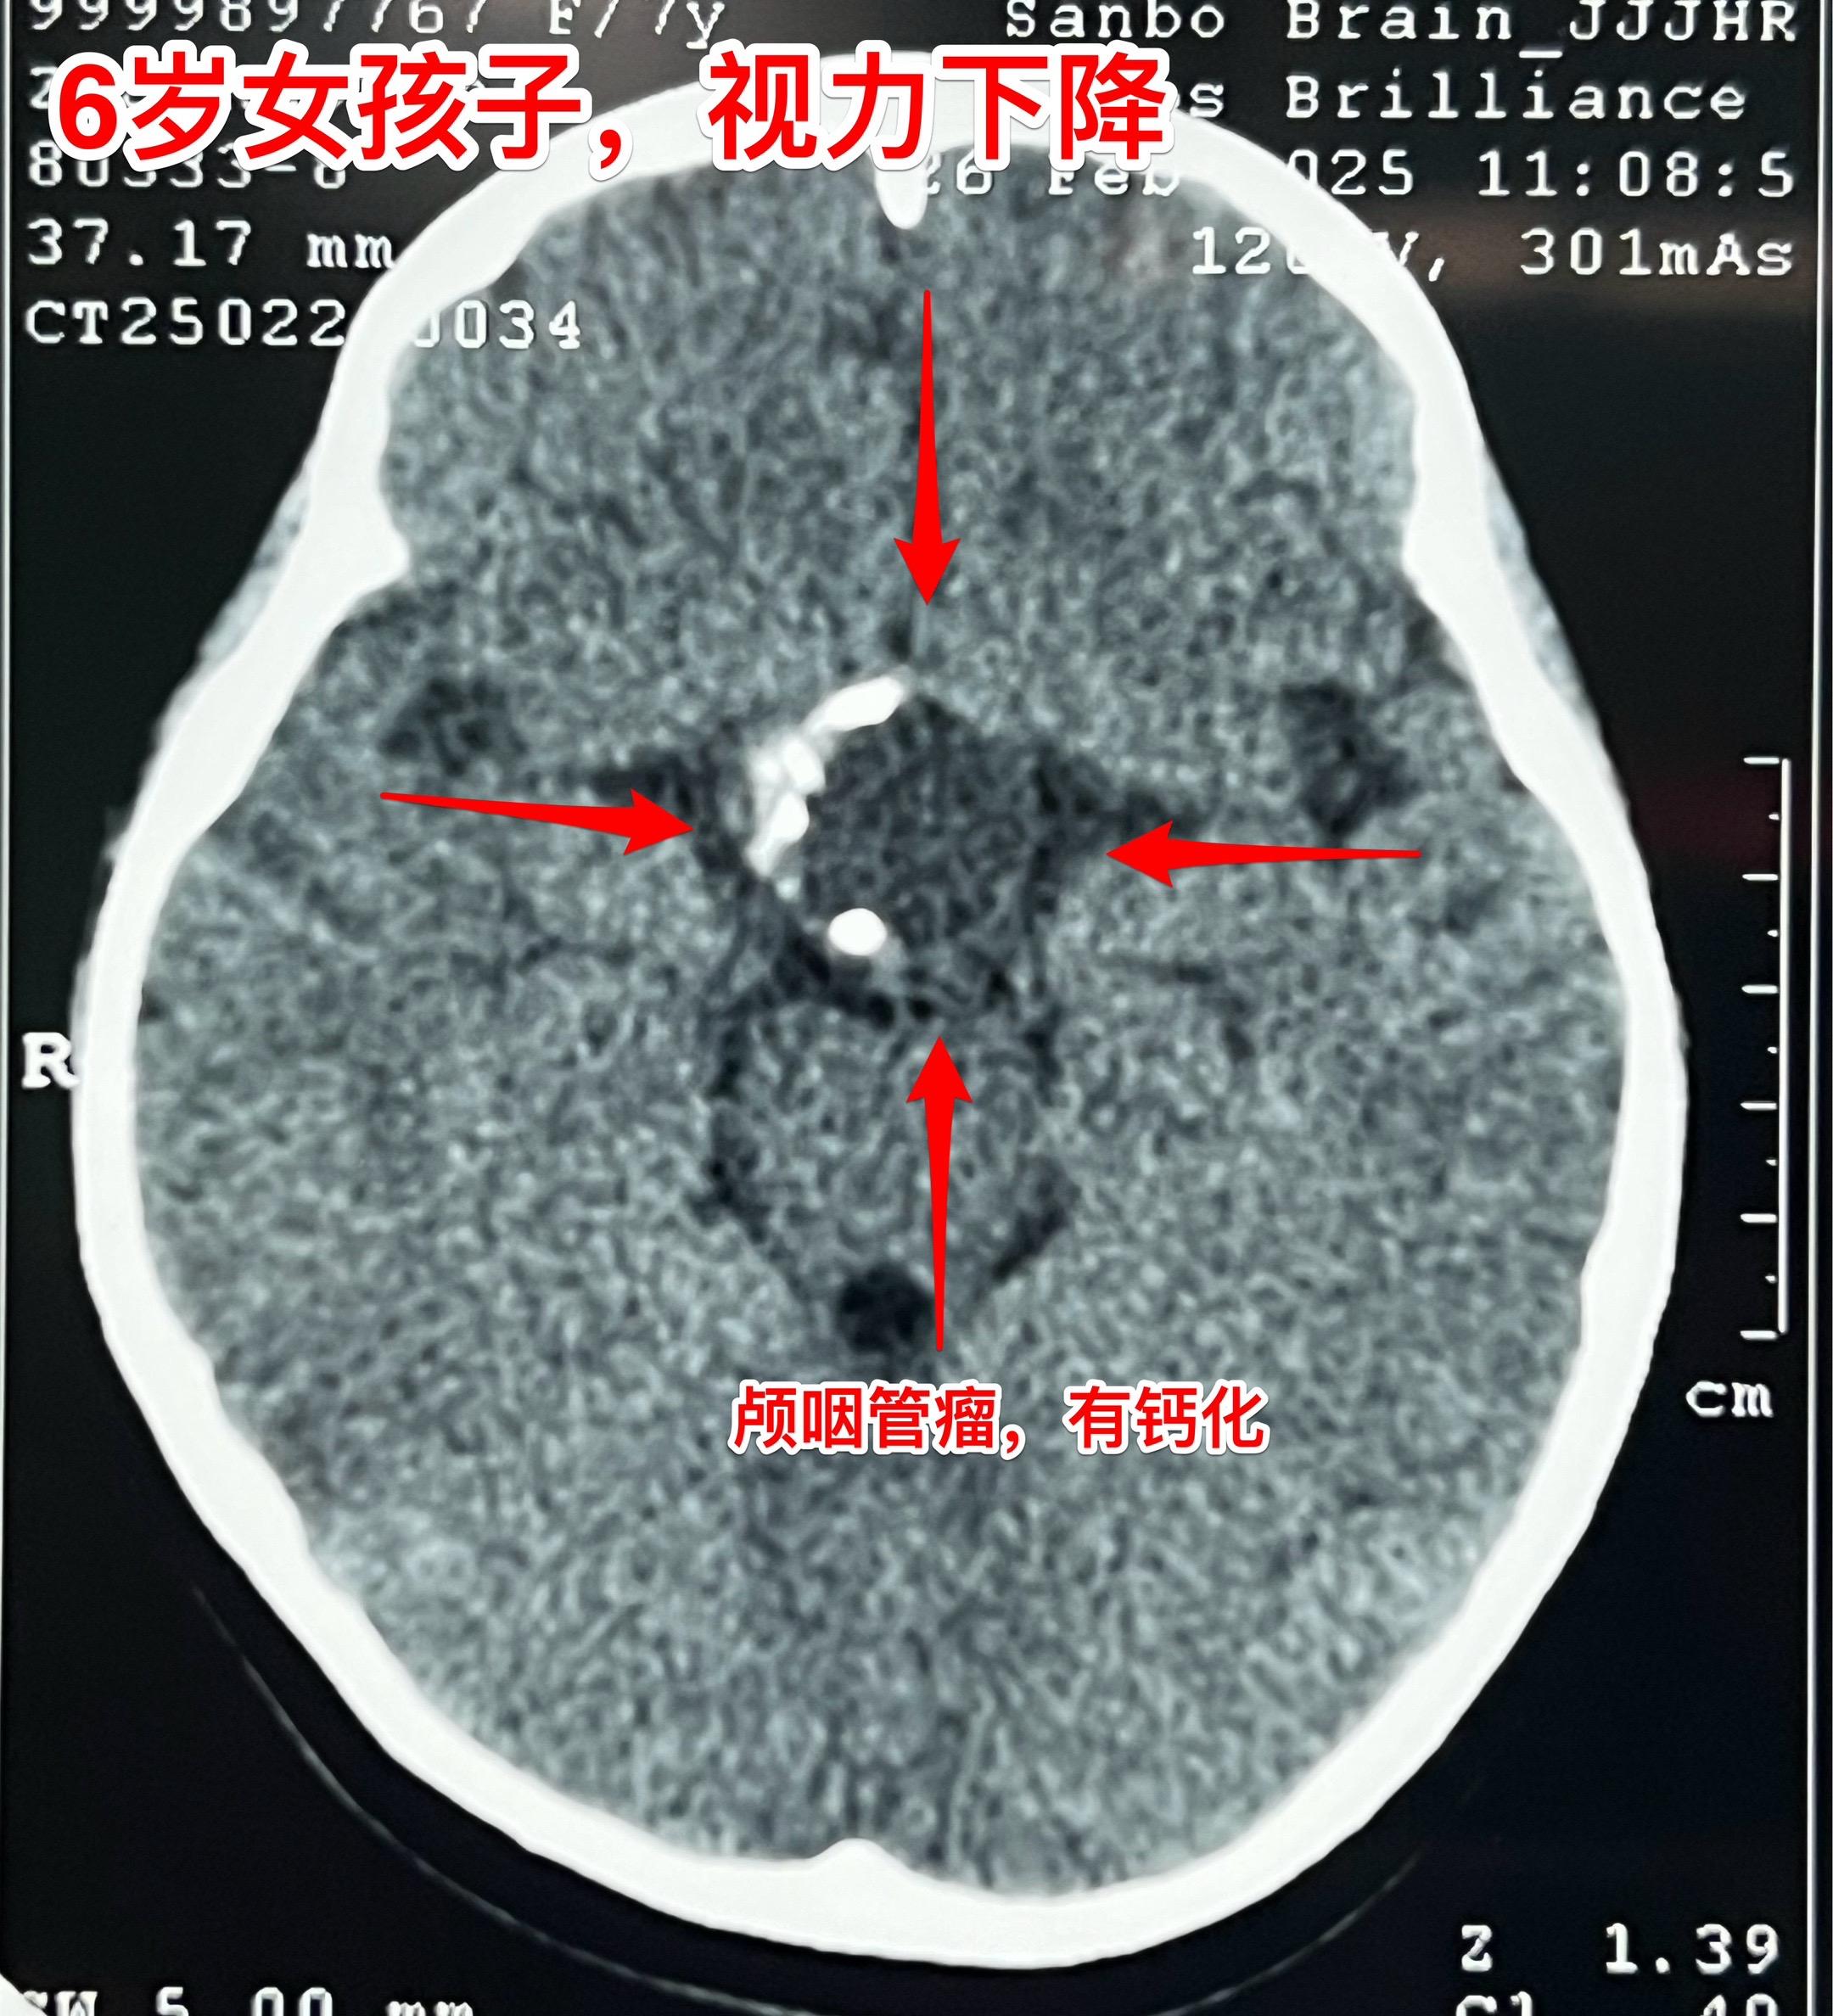

小学生的视力家长一定要关注。小学生因岁数小,对视力下降很可能并不知道表述。所以家长一定要密切观察孩子的视力变化。如果 孩子在很近距离才能看清书上的字,或者看电视距离时喜欢靠近电视机很近才能看清楚,家长就要想到孩子的视力出了问题。我在之前的视频中曾经提到过类似的悲惨事件。 今天说的是六岁郑州小女孩,于2月22日在家写字时居然无法看清作业本上的方格了!家长这才发现孩子的视力很差了,快接近失明了。 2月23日行磁共振检查,发现鞍区肿瘤。3月25日行CT检查,发现肿瘤有钙化,可以确诊